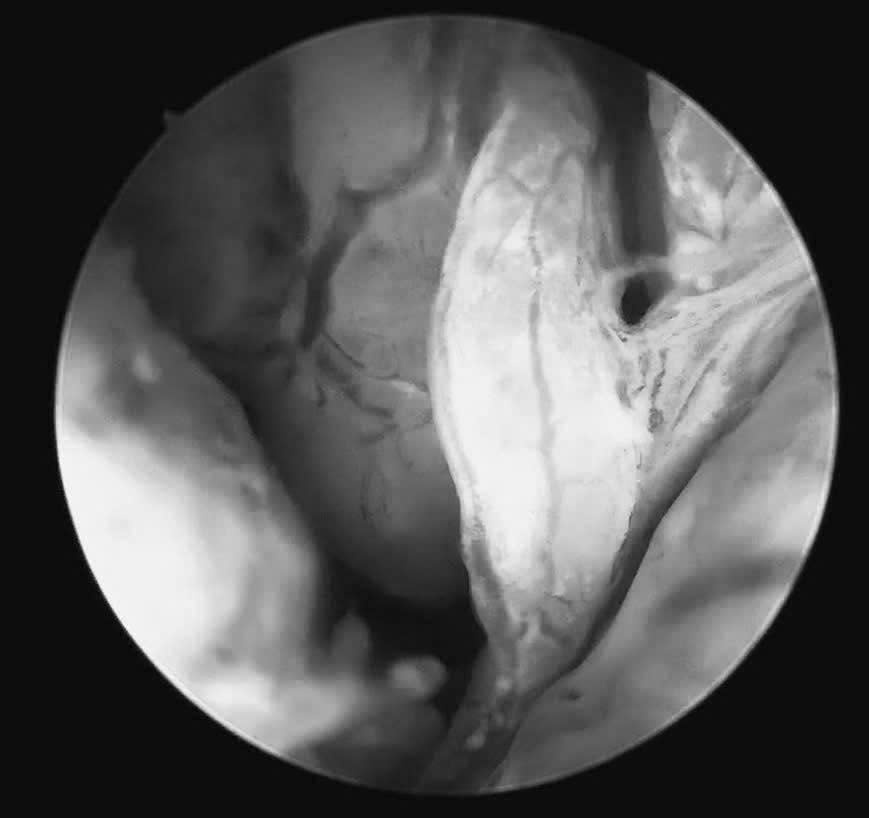

Chỉ đến khi được soi buồng tử cung bằng ống soi nhỏ, không tổn thương màng trinh, tổn thương ác tính mới được phát hiện.

👉 Ca thủ thuật được chính ThS.BSCKII Nguyễn Biên Thùy trực tiếp thực hiện, diễn ra nhẹ nhàng, an toàn. Hình ảnh ghi nhận: niêm mạc nham nhở, tăng sinh không đồng đều, mạch máu bất thường – những dấu hiệu cảnh báo rõ ràng tổn thương ác tính.